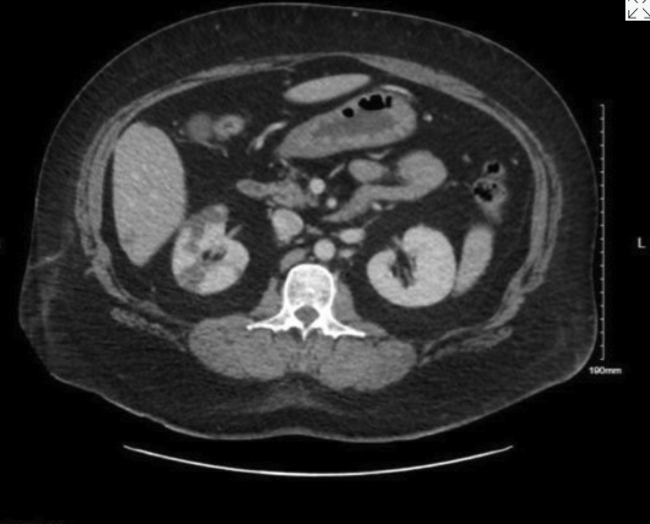

A 46-year-old nonsmoking woman with a medical history of hypertension, hyperlipidemia, type I diabetes, and duodenal cancer with a BRCA gene mutation underwent bilateral skin-sparing mastectomies and immediate deep inferior epigastric perforator (DIEP) flap reconstruction. She received preoperative subcutaneous heparin and intraoperative heparinized saline flushes. On postoperative day 10, she presented with chest pressure, nausea, and vomiting. Computed tomography imaging revealed a right renal infarct (Figure 1). Exam findings included blanching erythema and large blisters over the DIEP flaps (Figure 2). Surgical reexploration confirmed patent DIEP pedicles with presumed bilateral intraflap microthrombosis compromising skin paddle perfusion. Following administration of intravenous (IV) heparin, the patient developed severe vasodilatory shock and cardiac arrest requiring cardiopulmonary resuscitation. There was a return of spontaneous circulation after administration of epinephrine, suggesting an anaphylactic reaction. She was diagnosed with heparin-induced thrombocytopenia (HIT) based on a positive platelet factor 4 (PF4) antibody and serotonin release assay. She was transitioned to argatroban and later discharged on apixaban. The patient ultimately experienced partial flap loss but recovered well. The flaps successfully integrated, and no further issues were encountered in the long term.

Figure 2. Deep inferior epigastric perforator flaps demonstrating blanching erythema on exam and without doppler signals on postoperative day 10.